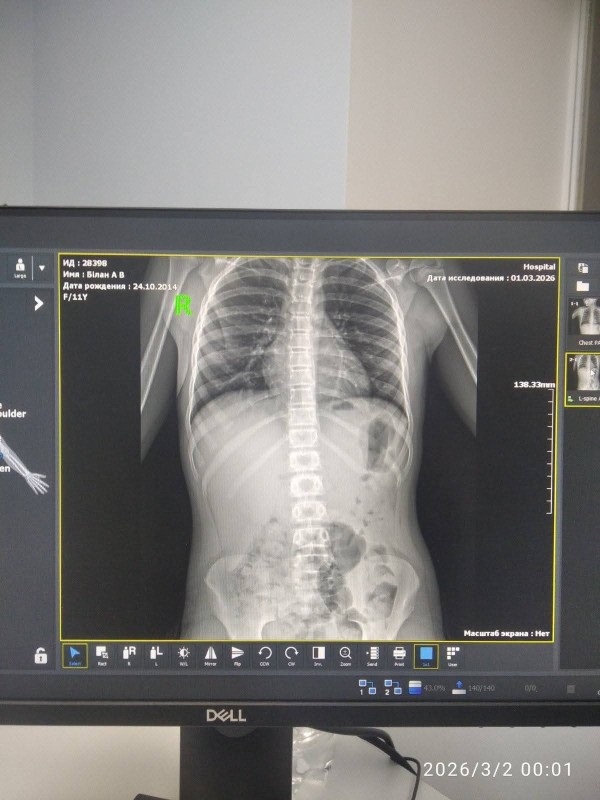

Згідно з випискою лікарні, у дівчини діагностували струс головного мозку, забій органів черевної порожнини та забої кінцівок. Мати дитини стверджує, що після інциденту не отримала жодної підтримки від адміністрації навчального закладу.

Знімок тулубу дівчинки . Фото з архіву Яни Білан